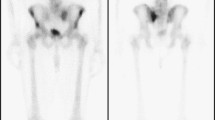

Currently, BPs are the mainstay for long-term treatment of osteolytic bone disease and are used as bone-specific palliative treatments to reduce skeletal complications from bone-metastasizing tumors. They have been shown useful in treating prostate, breast, and lung cancer that metastasize to the skeleton [54–56]. We have recently reported on the action of BPs on development and growth progression of experimental bone metastasis [44]. BLI was used for the detection, monitoring and quantification of bone metastases induced by intracardiac or intraosseous injection of MDA-231-B/luc+ in nude mice. The bisphosphonate olpadronate strongly inhibited tumor-induced osteolysis and its suppression of bone turnover, before bone colonization by intracardially injected cancer cells, significantly inhibited the number of developing bone metastases. Tumor growth in the few, but still developing bone metastases, was affected only transiently. Bone turnover reduction, however, had no effect on the growth and progression of established bone metastases as shown after intraosseous injection of cells (Fig. 1).

Effects of bisphosphonate treatment on intrabone growth of MDA-231-B/luc+ breast cancer cells (BLI) and osteolysis (radiography) in tibiae of 6-week-old female nude mice. MDA-231-B/luc+ cells (1 × 105 cells) were inoculated directly into the right tibia of nude mice (n = 5) that were having a continuous release of high dose of olpadronate by osmotic mini-pumps (16 μmol/kg/day, 24 h/day for 28 days). a Effect on intrabone tumor growth was detected by BLI as described [36]. RLU = relative light units. b Effect on development of osteolytic lesions as assessed radiographically lytic area in mm2. c representative animals of the olpadronate treated and vehicle treated groups (BLI and radiography). Reproduced from [44]